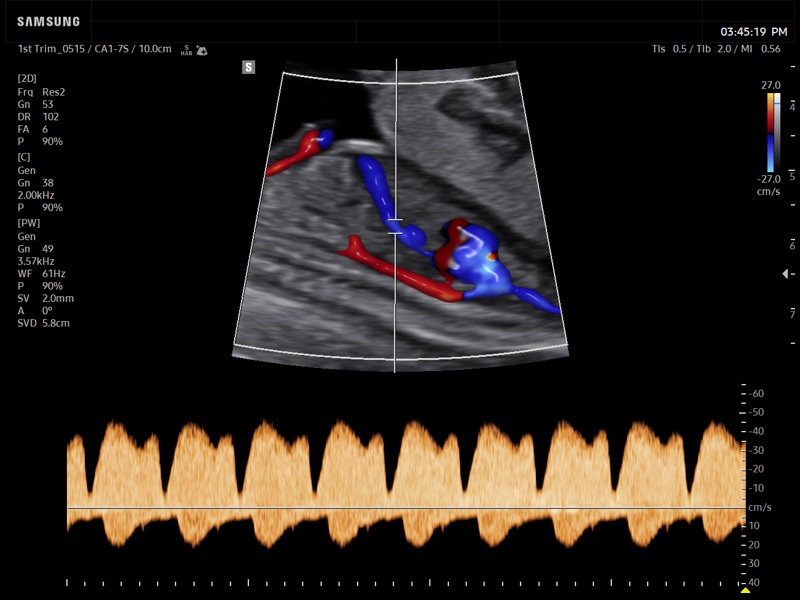

[RU] Ultrasound image №939: Fetal heart (ductus venosus) in CFM (color flow mapping) and PW (pulsed wave) mode. 1-st trimester, convex probe 1-7 MHz.

Echogramm was received by ultrasound scanner Z20 (new model).